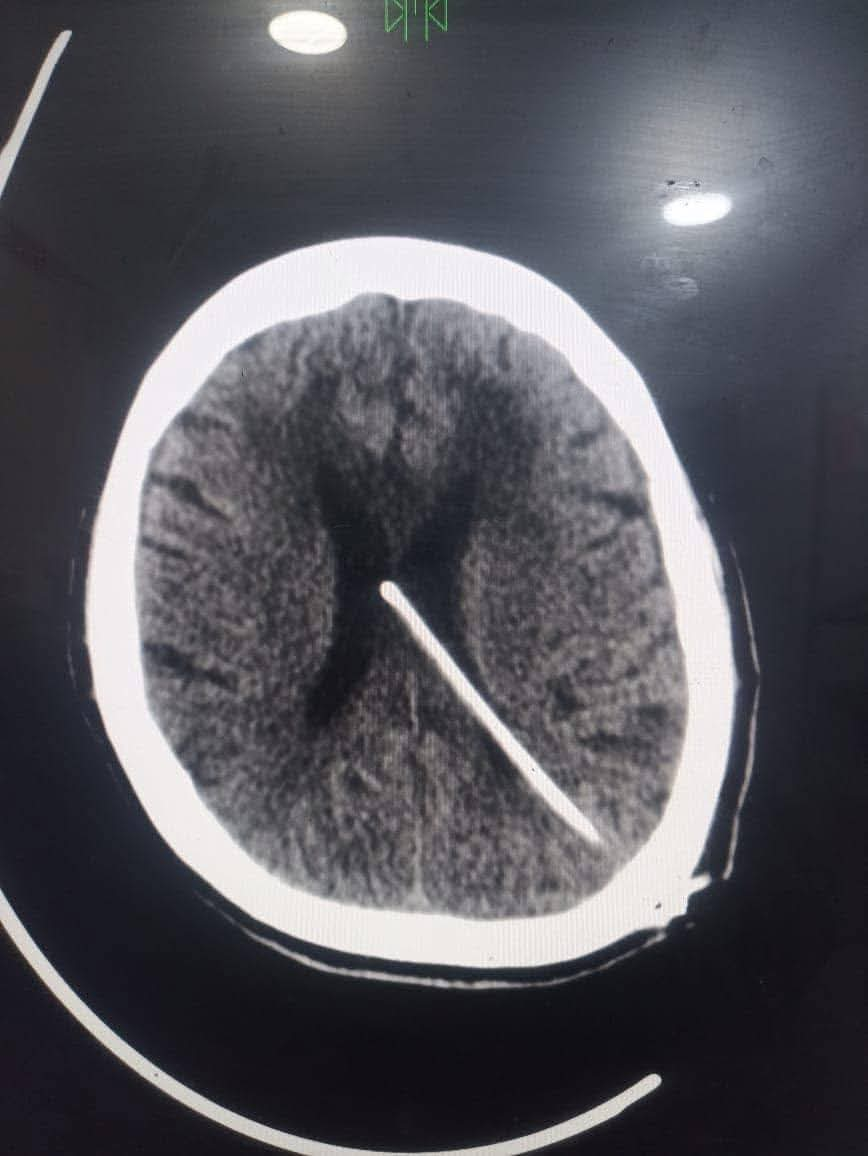

أجرى الفريق الطبى بمستشفى دمياط العام بقيادة الدكتور معاذ ياسر العبد جراحة دقيقة لتركيب صمام مخى بريتونى لمريضة تعانى من فشل كلوي وغيبوبة.

حيث تم إجراء الفحوصات اللازمة لها قبل إجراء الجراحة والتى تبين خلالها من وجود استسقاء حاد بالمخ أثر على درجة الوعى والحركة، وعليه تم التعاون مع كافة الأقسام للتجهيز لإجراء الجراحة وتركيب الصمام لصرف ضغط السائل النخاعى الزائد وخروج الحالة بدرجة وعى كاملة بعد نجاح العملية، والتى تُعد الأولى من نوعها بمستشفيات مديرية الصحة بدمياط، فى إطار الجهود المبذولة للقضاء على قوائم الانتظار بتخصص جراحات المخ والأعصاب